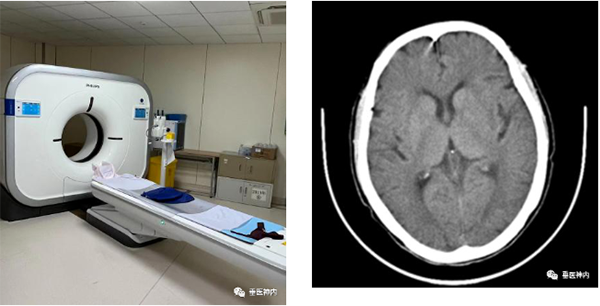

一、头颅CT

CT(Computed Tomography),即电子计算机断层扫描,它是利用精确准直的X线束,与灵敏度极高的探测器一同围绕人体的某一部位作一个接一个的断面扫描,具有扫描时间快,图像清晰等特点,是急性脑血管病最常用的首选检查方法。优点是成像速度快,价格低廉,无需预约,无扫描条件限制,只要患者安静平躺几分钟即可完成。